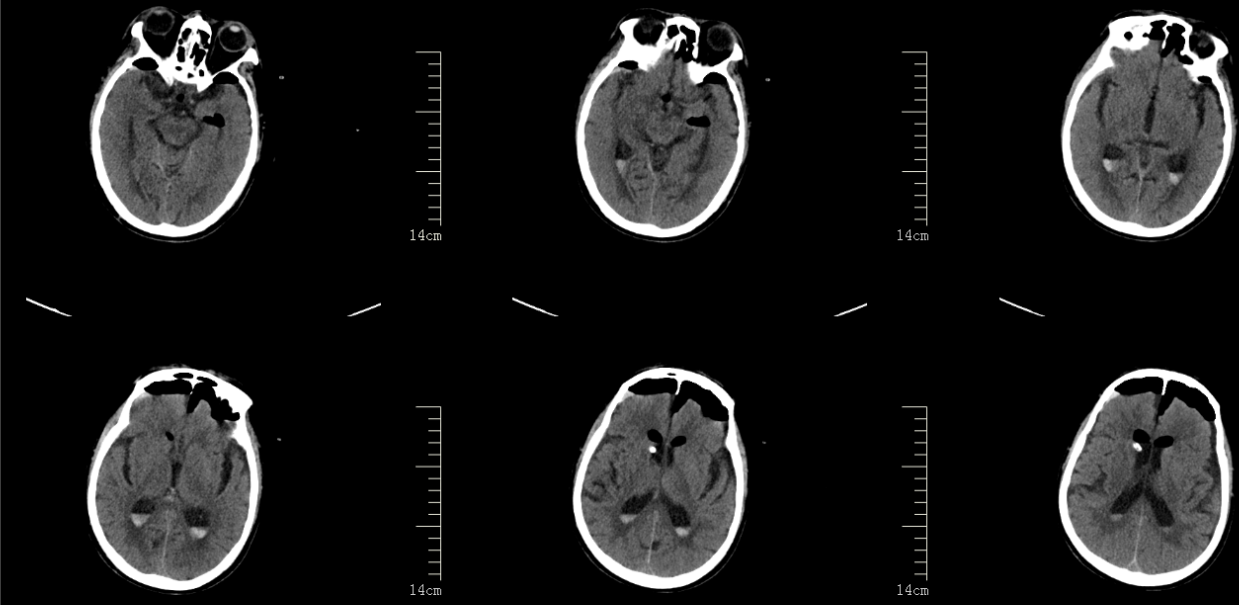

2024年12月22日中午,84岁的罗大爷刚与家人吃完饭,突然出现肢体活动障碍,随后意识也出现障碍。家属立即呼叫120,将其送往阆中市人民医院。急诊进行头颅 CT检查,结果显示脑干出血并破入脑室,伴有梗阻性脑积水。患者随即通过绿色抢救通道被送入神经外科。值班医生杨学明副主任医师接诊后发现,患者脑干部位积血量并不多,无需进行手术治疗,但破入脑室的积血却引发了致命问题——阻塞了脑脊液的循环通路。脑室内每天会产生350-550ml的脑脊液,正常情况下,脑脊液会沿着自身的循环通路被吸收,而循环通路一旦堵塞,意味着每天产生的脑脊液会积聚在脑子里,娇嫩的脑组织根本容纳不下这么多液体。

针对这一情况,神经外科李想主任立即组织手术组医师开展病情讨论,并制定了具体治疗方案:立即施行三脑室底造瘘+侧脑室置管外引流术。在麻醉科团队的全力配合下,手术由杨学明副主任医师与张珩副主任医师联合主刀,不到 2小时便顺利完成。术后复查CT显示,患者的脑积水症状已消失,脑室原有的积血也已完全吸收不见。术后5天,顺利拔除侧脑室引流管;19天后,患者顺利出院进行康复锻炼,随访至今未再出现脑积水。

术前影像

术后影像